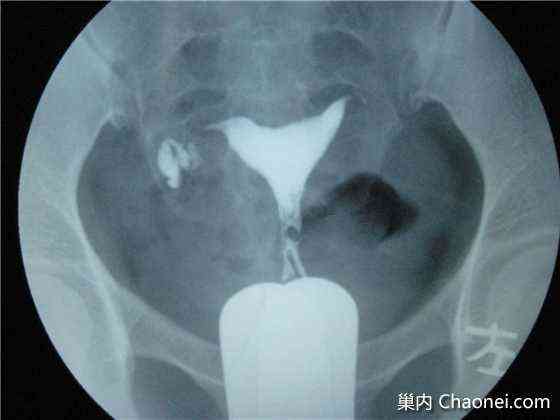

摘要:通草具有疏通输卵管堵塞的功效与作用。作为一种中药材,通草被广泛用于妇科领域,能够帮助疏通输卵管,提高受孕几率。其疗效受到许多女性的认可。通过服用通草,可以有效缓解输卵管堵塞带来的不适,促进血液流通,有助于恢复输卵管的正常功能。对于具体的疗效,还需根据个人体质和病情而定。

通草不仅可以帮助我们维持身体的正常功能,如促进血液循环、改善代谢等,更在女性健康方面发挥了重要作用,它能够减少体内炎症、改善血液流通,从而有助于输卵管的通畅,许多使用者的积极反馈都证明了通草在这一方面的显著效果。